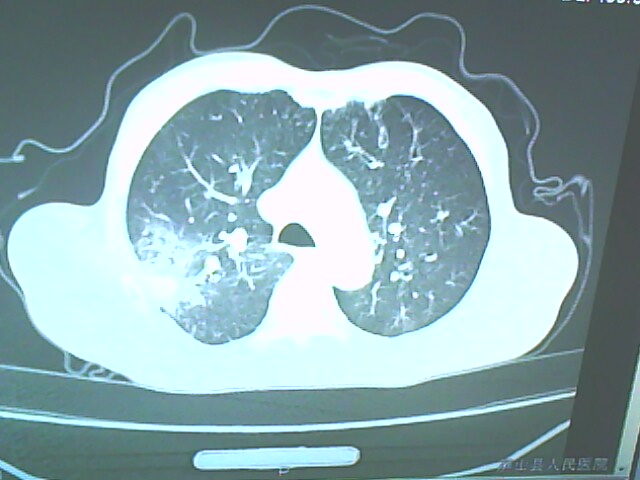

患者,男,66岁,以咳嗽、咳痰伴胸痛来就诊。

胸片提示右上肺占位病变。请各位老师看看ct。

考虑癌性空洞可能性大,空洞内壁不规则,病灶周围模糊,分叶、有毛刺

空洞内壁不规则,病灶周围模糊,分叶、毛刺呈日光放射状,突然截断,支持考虑癌性空洞

考虑右肺上叶后段周围型肺癌并癌性空洞形成。

考虑癌性空洞可能性大,内壁不规则,洞壁薄厚不均呈结节状突起,边缘模糊,分叶,毛刺

右上肺后段肺癌:

典型癌性空洞(偏心性,壁厚薄不均,内壁不光整),周围毛刺较僵硬,且有刺突征和血管聚集征